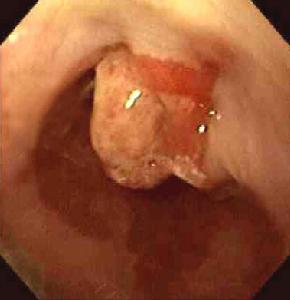

3.纖維食管鏡檢查 可見到凸入食管腔內的腫物,一般不作鏡檢,以免造成組織粘連影響手術治療。